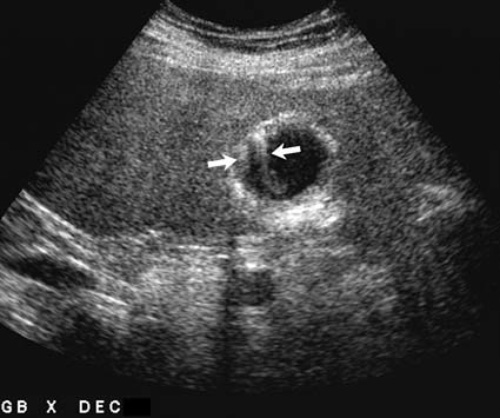

Артефакт «хвост кометы» является вариантом реверберации, возникающий при проникновении ультразвука в кристалл холестерина, что вызывает внутреннее отражение волн перед возвратом к датчику. Нужно отметить, что каждое дополнительное отражение образует дополнительное ложное эхо, которое располагается глубже истинного. Из-за того, что каждое дополнительное отражение приводит к ослабеванию волны, каждое более глубоко расположенное эхо обладает меньшими размерами, в результате чего образуется V-образный артефакт, описываемый как «хвост кометы» (рисунок 3).

Рисунок 3. УЗИ желчного пузыря: Артефакт «хвост кометы» (стрелки) характеризуется наличием параллельно сужающихся эхо, которые образуют реверберации внутри кристаллов холестерина в стенке желчного пузыря

Артефакт «хвост кометы» информативен при выявлении кристаллов холестерина в желчном пузыре, а также при диагностике полипов и аденомиоматоза. Также «хвост кометы» образуется при наличии металлических предметов, например, хирургических скрепок.